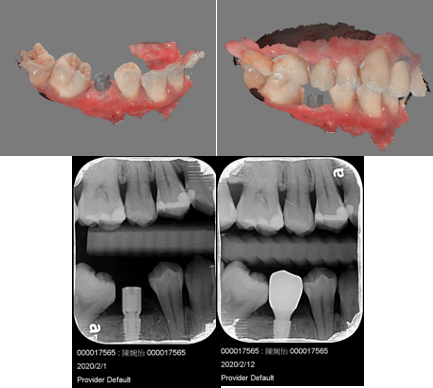

在斷層掃描的 3D 圖疊合牙齒的掃描圖,即可在疊合圖上設計植牙的位置,以此輸出的導引板上設有卡準,植牙器械順著這個卡準,植牙位置超精準,手術速度也會快很多,更能避免傷到重要的神經血管,安全、快速、舒適一次到位。